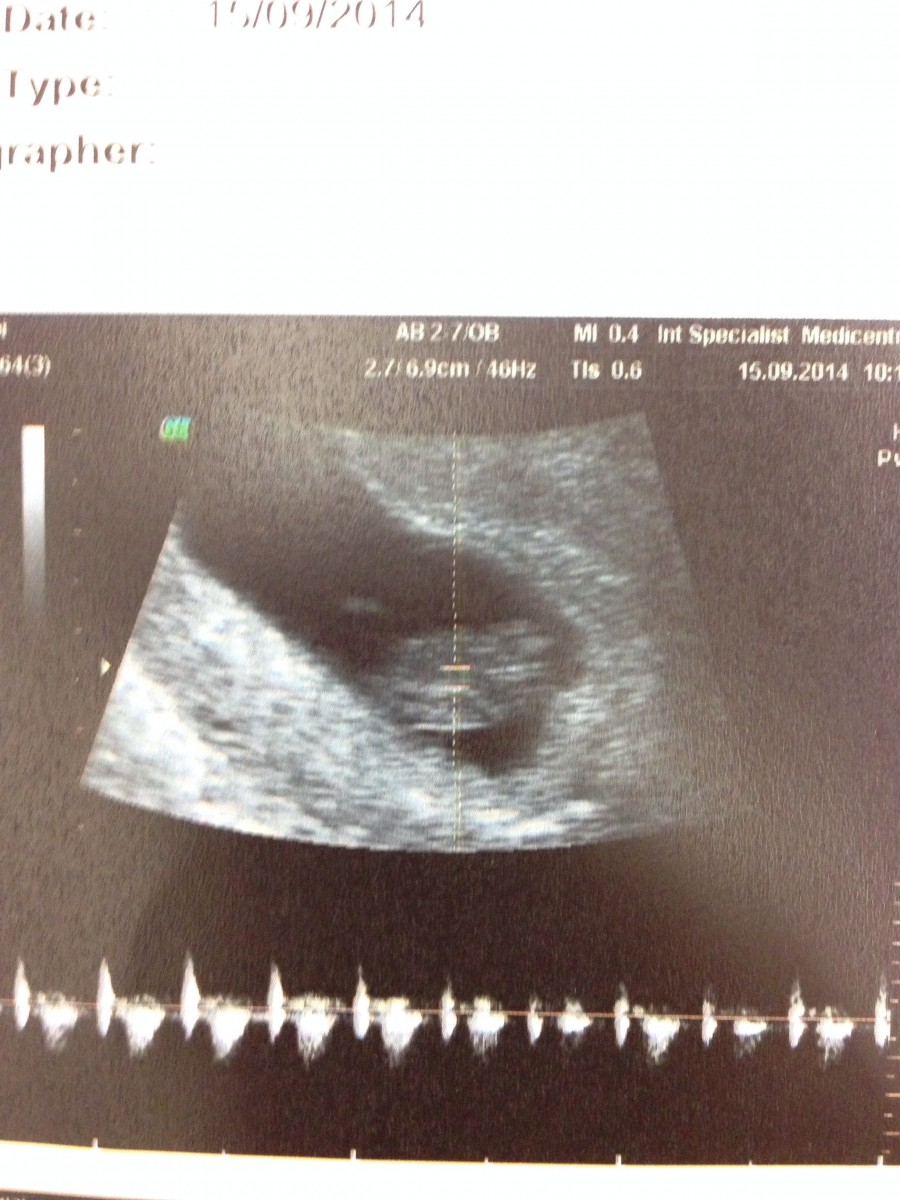

佢安好呀~1.72cm,有心跳了﹗雖然係mon上面嘅BB呱依然係一團白色嘅東東,但我哋聽到佢每分鐘150下左右嘅「噗通噗通噗通⋯」時,感覺好實在~感謝主﹗﹗悶悶唔係我想像出來的,你真係成長緊丫﹗我要更注意飲食、更注意休息、更用心飲藥了,你要生生性性呀~媽媽錫錫﹗chu~